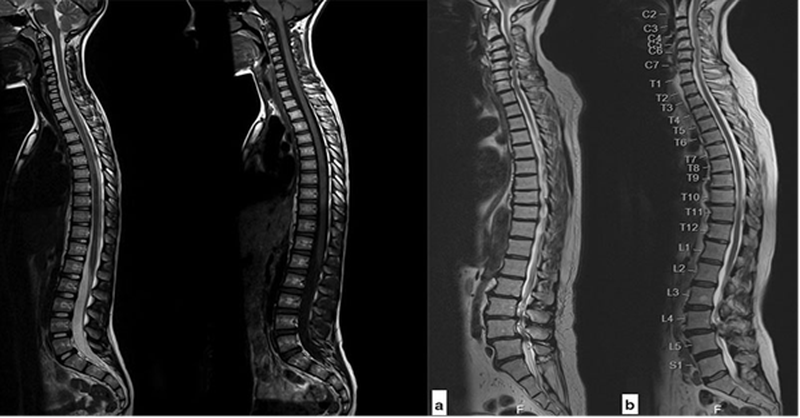

- Hình ảnh cộng hưởng từ (MRI) cột sống thắt lưng: Xác định chính xác loại tổn thương và cả vị trí thoát vị, mức độ lan rộng của đĩa đệm và có thể phát hiện các nguyên nhân khác ít phổ biến hơn (viêm đĩa đệm, đĩa đệm cột sống, khối u,...).

Hình ảnh cộng hưởng từ (MRI) cột sống thắt lưng sẽ giúp xác định chính xác loại tổn thương